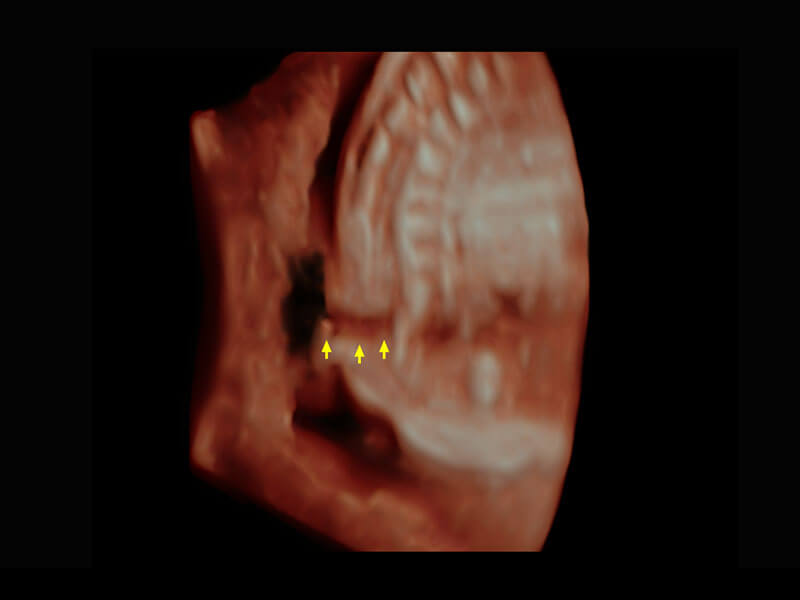

胎心筛查

P60搭载一系列胎儿心脏成像技术,实现精细的胎儿心脏评估。

• 胎心容积成像